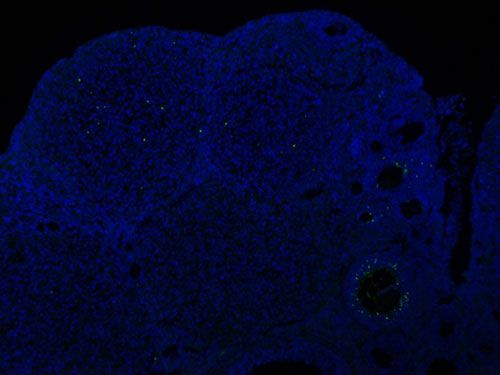

實(shí)驗(yàn)結(jié)果展示:

TUNEL(熒光)檢測(cè)-小鼠卵巢